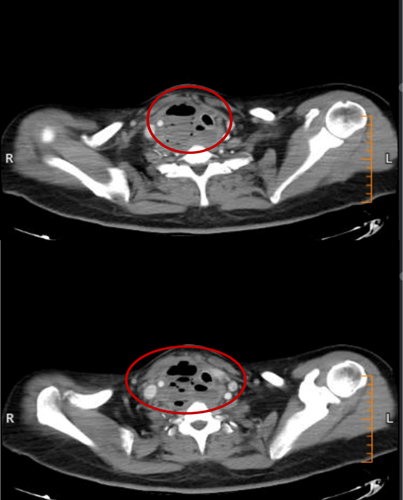

2月15日、2月20日,当长沙沉浸在辞旧迎新的欢声笑语中,两位病情凶险的颈部深部脓肿患者先后被推入耳鼻咽喉头颈外科。他们都有多年糖尿病病史,春节期间饮食不规律、作息紊乱、血糖波动大,让原本隐匿的感染如野火般迅速蔓延。其中一位患者的感染已突破颈部间隙,如藤蔓般向下侵入纵隔区域——那里是心脏、大血管、气管的“交通枢纽”,是人体最脆弱的生命禁区之一。CT影像上,脓肿中密布的气腔像一个个危险的信号,气管严重受压,每一次呼吸都变得艰难。而临床研究数据表明,颈深部脓肿并发下行性纵隔炎,病死率为40%~70%。患者的生命,危在旦夕。

患者甲CT示:颈部及纵隔脓肿,脓肿中含有多个气腔